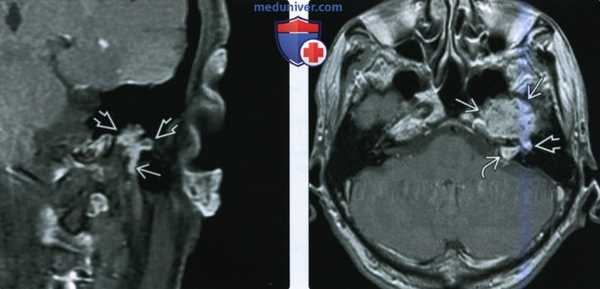

(Слева) На рисунке в аксиальной плоскости показана крупная шваннома лицевого нерва (ШЛН), состоящая из компонентов ММУ («мороженое») и ВСК («рожок»), напоминающая вестибулярную шванному. Поражение лабиринтного сегмента лицевого нерва позволяет сделать заключение.

(Справа) При аксиальной MPT T1 ВИ С+ FS у пациента с односторонней ней-росенсорной тугоухостью визуализируется ШЛН с компонентами ММУ и ВСК. Обратите внимание на «хвост» лабиринтного сегмента лицевого нерва, позволяющий отличить ШЛН от вестибулярной шванномы.

(Слева) При аксиальной МРТ Т1 ВИ С+ у пациента с парезом лица определяется С+ ШЛН с поражением ММУ, ВСК, лабиринтного сегмента, коленчатого ганглия ЧН VII. Если ШЛН ограничена ВСК, она в точности напоминает вестибулярную шванному.

(Справа) При аксиальной тонкосрезовой МРТ Т2 с увеличением в области дна ВСК слева у пациента с нейрофиброматозом 2 типа визуализируются шванномы верхнего преддверного и лицевого нервов. Внимание: при НФ2 не все опухоли в ВСК являются шванномами.